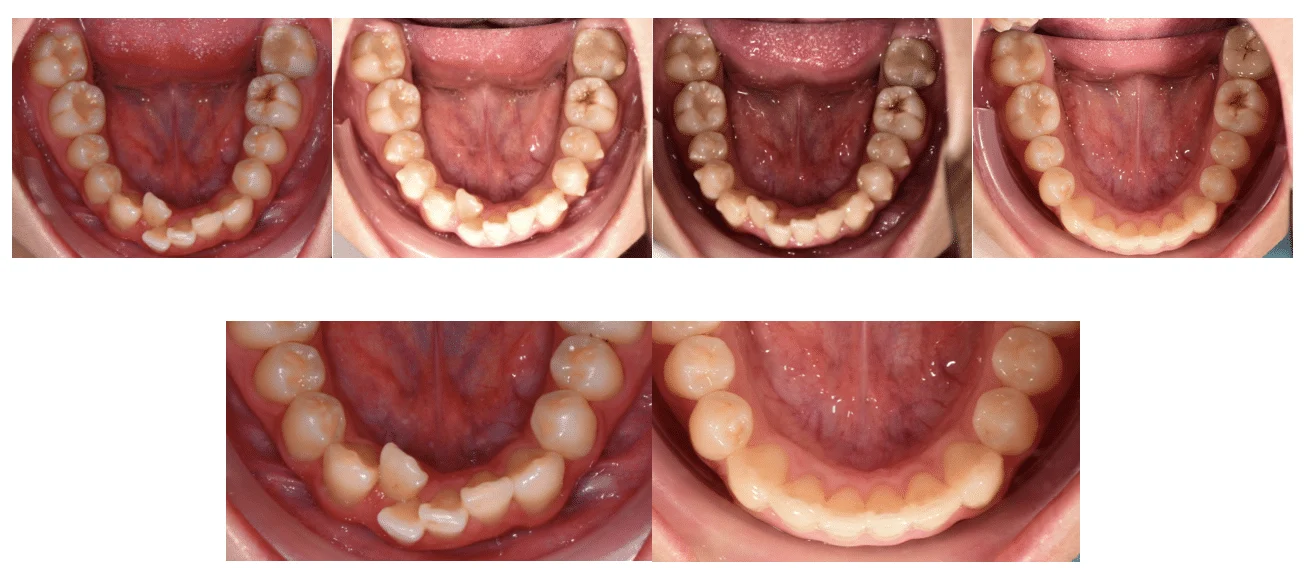

矯正案例-齒列擁擠

Case

案例分享